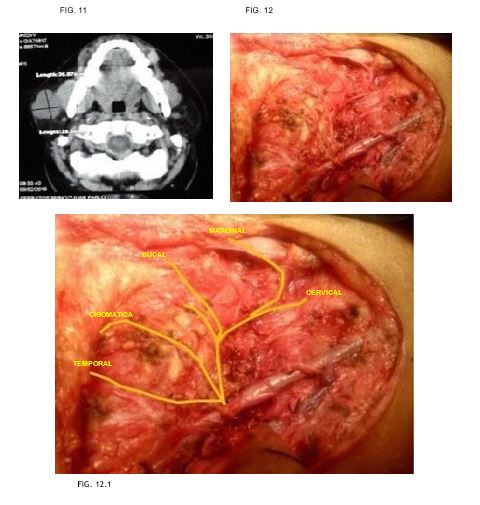

Caso 6: masculino de 23 años de edad, sin antecedentes de importancia, con tumor parotídeo izquierdo sometido a parotidectomía supraneural resultando en adenoma pleomorfo. (FIG. 11-12)

7